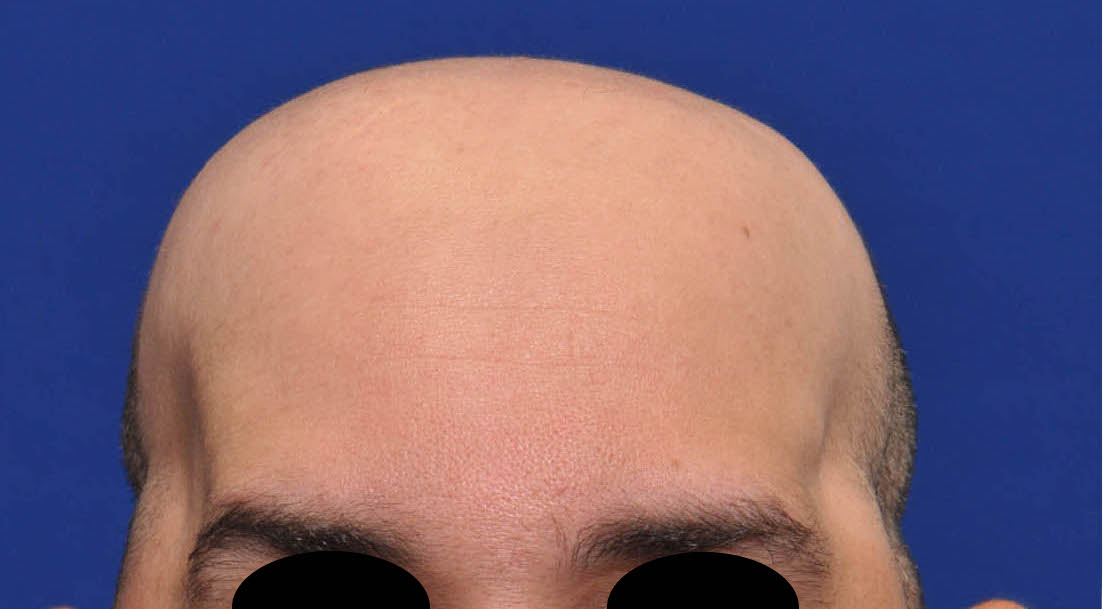

Patient 100

Desire for reshaping of an asymmetric flat back of the head in a shaved head male.

A combined back of the head reshaping procedure was done with a custom skull implant, sagittal ridge reduction and a right temporal muscle reduction.